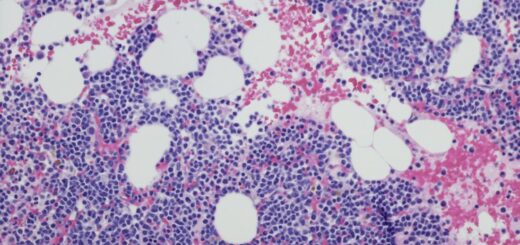

(Dit is een minieme bewerking van een draadje dat ik afgelopen zaterdagavond op X/Twitter tikte.) (1) Ik lig inmiddels al zes dagen in het ziekenhuis. De redenen daarvoor zijn vrij desastreus maar hier even niet relevant. Hier een draadje over...